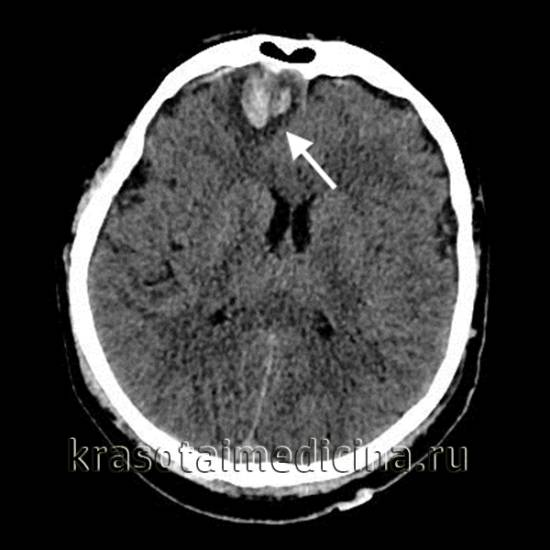

Основным методом диагностики ушибов головного мозга (УГМ) является компьютерная томография (КТ). Томографическая картина зависит от тяжести ушиба. При легкой степени очаги с пониженной плотностью выявляются лишь в 40-50% случаев. В зоне ушиба на томограммах наблюдаются отечность и петехиальные кровоизлияния. Отек может охватывать всю долю мозга или даже целое полушарие, что приводит к умеренному сужению ликворных пространств.

На аксиальной КТ головного мозга без контрастного усиления определяется контузионный очаг в правой лобной доле, представленный геморрагическим компонентом, зоной детрита и отека.

Ушиб средней тяжести характеризуется наличием очагов ушиба в виде зон пониженной плотности. При геморрагическом пропитывании очаг может иметь повышенную плотность. При тяжелом ушибе томография показывает очаги как повышенной, так и пониженной плотности. Повышенная плотность указывает на сгустки крови, а пониженная — на участки размозжения и отека. При крайне тяжелых поражениях зона деструкции церебральной ткани проникает в подкорковые структуры.

КТ также проводят в динамике в ходе лечения. Наблюдения показывают, что при легкой или средней тяжести ушиба со временем происходит полное исчезновение очаговых изменений. При тяжелом УГМ отмечается уменьшение площади очагов деструкции, а затем их трансформация в кисты головного мозга или участки атрофии. Чем тяжелее черепно-мозговая травма, тем медленнее проходят указанные изменения, визуализируемые при помощи КТ.